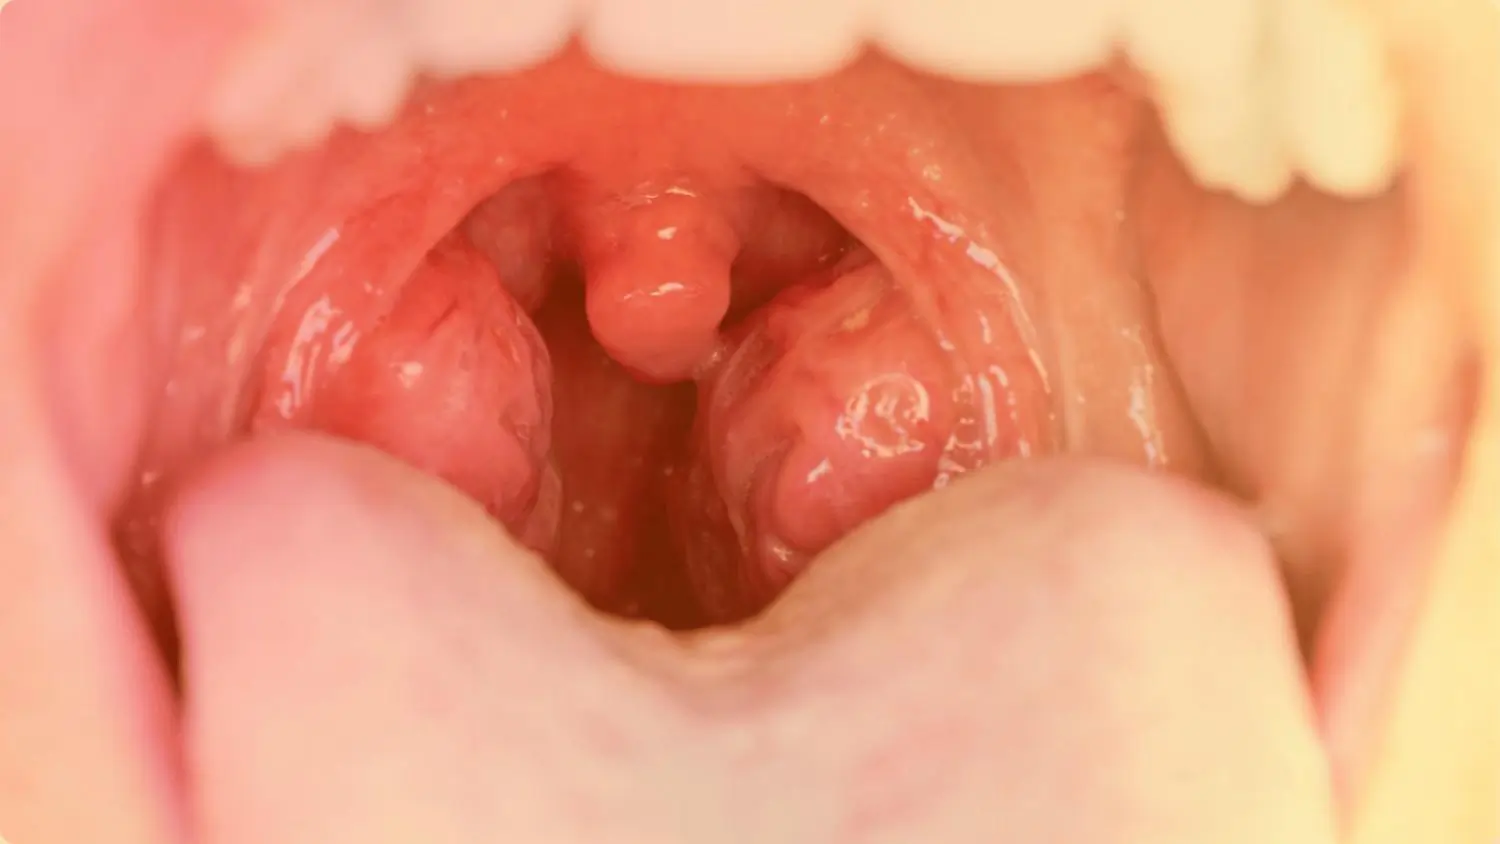

- Tonsillitis